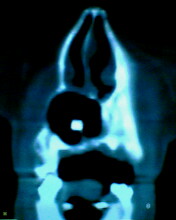

患者:男71岁,右侧上颚肿物无痛性生长7年.

右上颌骨近中线部见类圆形低密度区,上方见一液平,周围见一薄硬化环,前下方见一牙根,后方累及水平板。上方突入鼻腔前下部,下方突入口腔。

考虑:右侧上颌骨囊肿伴感染。